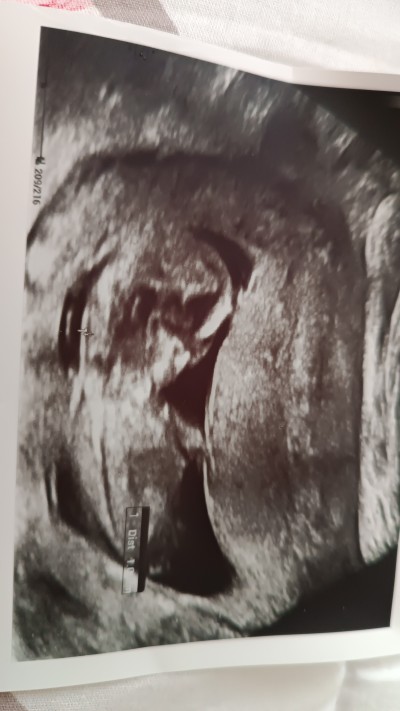

11 haftalık gebeyim burda kıza mı erkeğe mı benziyor sizce??

image